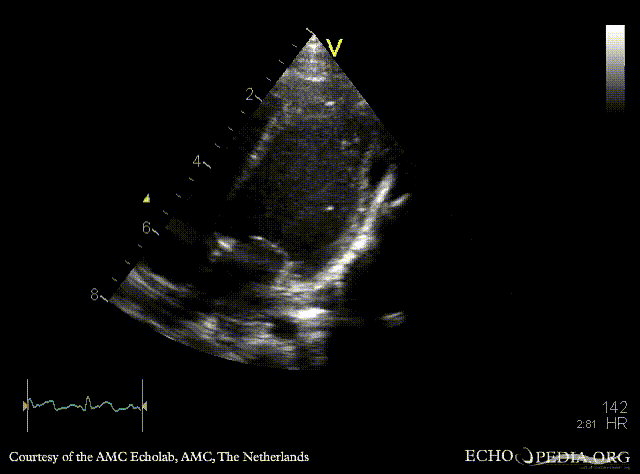

| Courtesy of: AMC Echolab, AMC, The Netherlands | |

| A4CH: pericardcyst | A4CH: pericardcyst, dimensions |